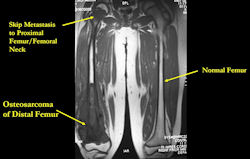

Skip metastases: metastases within the same bone, or across the joint in the adjacent bone, as the primary osteosarcoma

- spread via intraosseous or transarticular venous system within the bone

- rare; may occur without any evidence of pulmonary metastases

- traditionally associated with poor prognosis, although recent reports may suggest otherwise

- detection of skip metastases is important for surgical planning; occasionally, presence of skip metastases may dictate that the entire bone be surgically removed

MRI: Osteosarcoma of distal femur with skip metastasis to proximal femur

- detecting skip metastases

- Entire bone and adjacent joint should be visualized